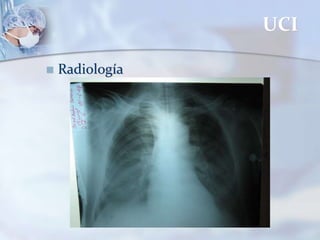

La unidad de cuidados intensivos (UCI) admite pacientes que requieren soporte ventilatorio y hemodinámico continuo así como monitorización. Una UCI requiere equipamiento como ventilación mecánica, desfibrilador, bombas de infusión, gasometría arterial, electrocardiografía y servicios de laboratorio y radiología. Existen diferentes tipos de UCI como neonatal, pediátrica, adulto, coronaria y quirúrgica.